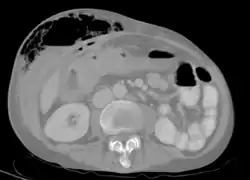

في الأشخاص الذين يعانون من الفشل الكلوي، والذين يحتاجون إلى غسيل الكلى، غالباً ما يتم إنشاء ناسور كيمينو بشكل متعمد في الذراع عن طريق جراحة قصيرة ليوم من أجل السماح بسحب الدم بشكل أسهل لغسيل الكلى. كعلاج جذري لارتفاع ضغط الدم البابي، ينتج الخلق الجراحي للناسور البابي الأجوفي تشابك بين الوريد البابي الكبدي وبين الوريد الأجوف السفلي عبر الفتحة الثربية (لوينسلو). هذا يعفي الجهاز الوريدي البابي من الضغط العالي الذي يمكن أن يسبب دوالي المريء، ورأس الميدوزا، والبواسير.